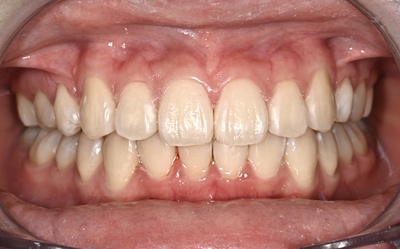

術後(現在治療終了後2年経過)

厳格には大臼歯部1級関係は構築できていないが、臼歯部、前歯部の静的、動的咬合はタイト確立できている。

大臼歯部1級関係を確実に構成しようとすると、下顎第一小臼歯も抜歯が必要と診断したが、治療期間の長期化、複雑化の観点から、また、全く虫歯のない歯牙をさらに2本抜歯することは疑問と判断。

良好な機能性と審美性が獲得できた。